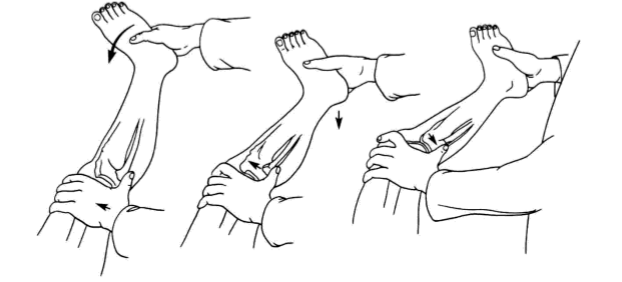

1、Lachman 试验

诊断 ACL 撕裂最敏感的检查,患者平卧,屈膝 15° ~ 20°,足置于床上。检查者一手抓住患者的股骨下端,一手抓住胫骨上端做方向相反的前后推动。

如有超过健侧的向前移动,则应视为阳性。

但必须注意区别是否从后沉位拉回正常位,抑或确为前移。此试验原意为检测前移,以明确 ACL,尤其是有利于判断 ACL 的前内束或后外束损伤。

2、前抽屉试验(ADT)

患者平卧,髋关节屈曲 45°,膝关节屈曲 90°,放松下肢肌肉。检查者坐在患者足部(方便固定其下肢),双手握住其胫骨上段,分别在中立位、内旋位、外旋位向前牵拉。

根据胫骨相对于股骨前移的程度与健侧做比较并进行分度:

- Ⅰ度:前移 0 ~ 5 mm;

- Ⅱ度:5 ~ 10 mm;

- Ⅲ度 > 10 mm。